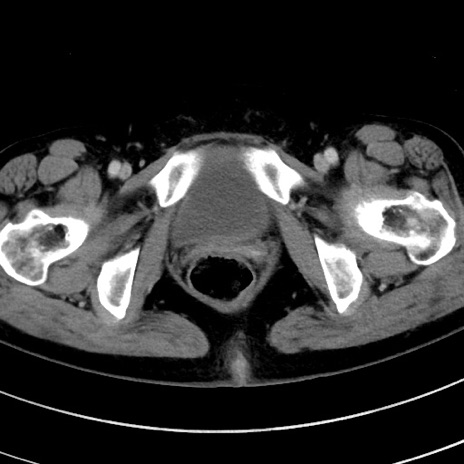

症例9(横断像)

【症例】 60歳代女性

【主訴】むかつき、みぞおちの痛み

【現病歴】3日前よりむかつきがあり、食事がとれない。

【既往歴】糖尿病

【身体所見】発熱なし、心窩部圧痛軽度あるも、腹膜刺激症状なし。

【データ】WBC 7400、CRP 1.92